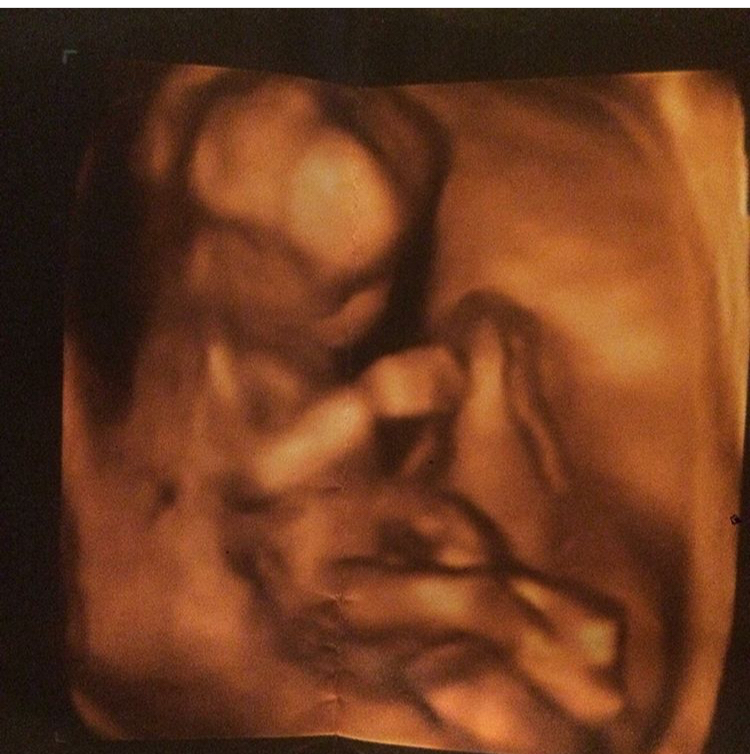

16 Haftalık Bebek Kaç Gram Olur

16 Haftalık Bebek Kaç Gram Olur.